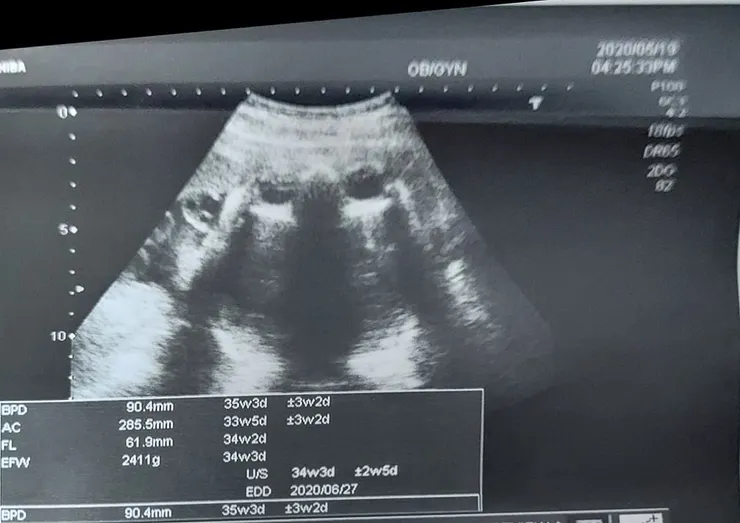

2020.5.16(六)PM10:35 (5.19--35W3D--2411G)

再來帶了好多問題去問醫生1.如果我現在開始按摩會陰部會不會到時候可以不用切開,然後醫生還問我那要怎麼按,有點無法說明白 因為網路上有,他的意思也是怕撕裂傷亂裂到時候更難好。2.我也問了會不會提早催生,他是說基本上不需要催生,除非超過預產期一周,3.再來我也很怕的護士推肚子,他是說現在不鼓勵,但是有例外,就說有的媽媽到時候沒力或是用不對力,寶寶差一點就出來了,那這時候就會幫忙一下,因為不能讓寶寶卡太久,總而言之就是說每個人不一樣,別人會發生的你不一定會發生,也不用太緊張,但是我就是會覺得別人發生的,我也有可能發生阿,還是有點擔心。

另外和大家分享一下今天產檢終於沒有這麼嚇人了,上次34週說寶寶3091克 頭95.5頭大了四週,因為32-34多了六百克,嚇死我了,30-32很努力吃燕麥才多了300克 後來放鬆一點吃了冰淇淋,布丁 豆花 但是真的都也只吃一點 還是多了600太恐怖,所以34-36週這兩星期我也很努力吃燕麥,今天的數字是 3297克 頭圍 95.9 天阿太幸運了,雖然之前大家都安慰我會有誤差 但是還是會緊張,我也努力相信有誤差 讓自己平安,雖然目前數字自己覺得可以接受 但是表示接下來還是要努力祈禱和克制 進行燕麥人生 超級超級感謝天主,也請大家繼續為我的順產祈禱 因為我真的覺得我是史上最怕痛的女孩。